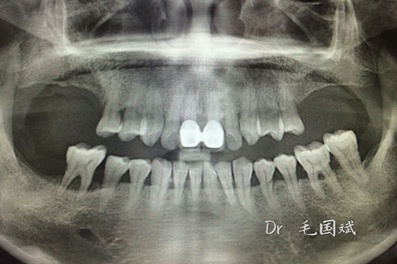

毛國斌種植病例——群討論分享